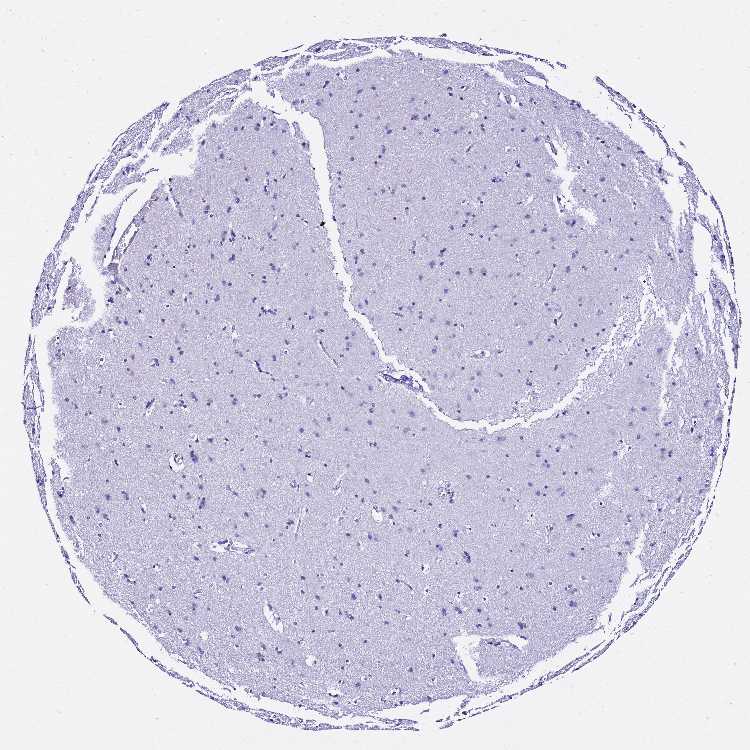

CEREBRAL CORTEX - Antibody stainingi

Antibody staining in the annotated cell types in the current human tissue is reported as not detected, low, medium, or high, based on conventional immunohistochemistry profiling in selected tissues. This score is based on the combination of the staining intensity and fraction of stained cells.

Each image is clickable and will lead to virtual microscopy that enables deeper exploration of all samples and also displays staining intensity scores, fraction scores and subcellular localization as well as patient and tissue information for each sample.

Antibody HPA045453

Endothelial cells Not detected

Glial cells Not detected

Neuronal cells Not detected

Neuropil Not detected